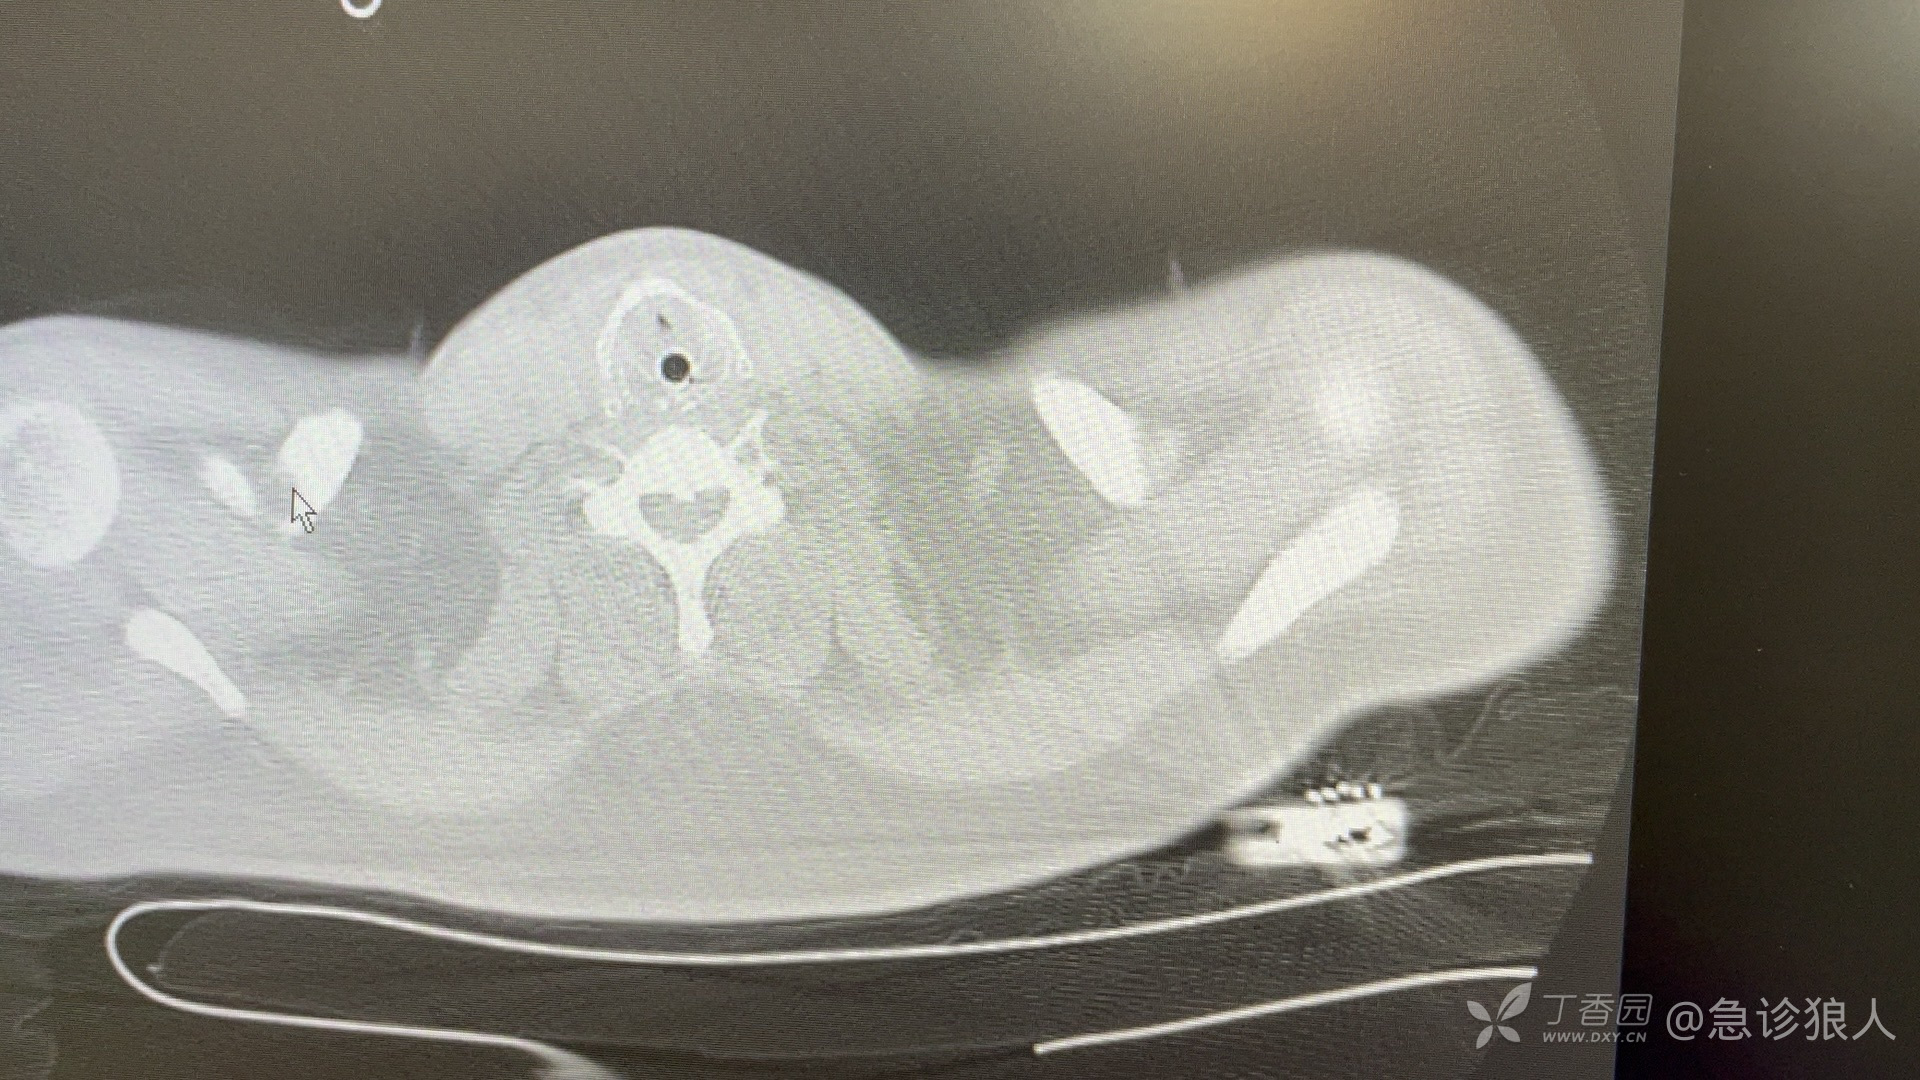

ct如下:

颅脑Ct未见明显异常!

看完胸部CT啥感觉?

对,误吸!

“看Ct是误吸了,让护士吸了痰,和胃里面的引流出来的一样,误吸导致的呼吸心跳骤停是没问题的!但是一瓶啤酒不会导致吧!为什么没吐出来呢?”